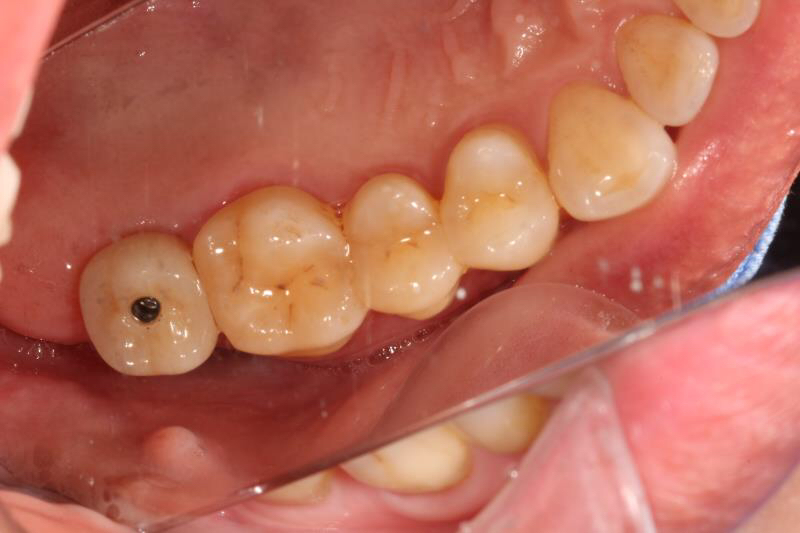

今天给大家分享的病例是一位中年女性,17缺失,由于长时间未修复,47伸长,留给17修复的空间不足。

老卢给她的治疗方案是:17种植修复,47根管治疗后截冠、高嵌体修复。这样可以最大限度的增加患者的咀嚼效率。

由于患者喉反射比较严重,种植牙冠和高嵌体都是用我们德国进口CEREC扫描制做的哦,与传统取模相比大大降低了不适感。